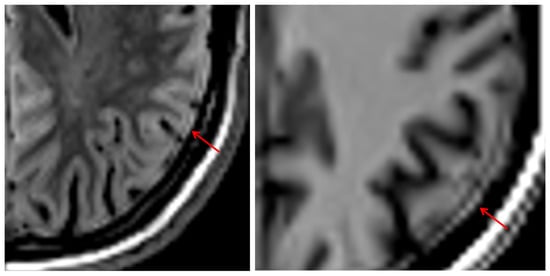

Clinical Image Quality and Reader Variability in 3D Synthetic Brain MRI Compared with Conventional MRI

Background/Objectives: This study evaluated the clinical image quality of three-dimensional synthetic MRI (3D SI) compared with conventional MRI (cMRI), focusing on tissue contrast, anatomical detail, and motion sensitivity. Methods: Patients with nonspecific neurological symptoms were included. Both cMRI and 3D SI were acquired on single-vendor 1.5 T and 3 T scanners with slice thicknesses of 1.0–1.7 mm. Two experienced neuroradiologists and one fellow independently evaluated matched scans using a 0–100 scale. Assessed parameters included signal-to-noise ratio (SNR), gray–white matter contrast, artifacts, motion robustness, and confidence in detecting perivascular spaces, white matter lesions, and subtle pathology. Interrater agreement was measured using Krippendorff’s alpha and ICC2. Multiple linear regression analyzed associations between image quality ratings and imaging method. Results: Images of 31 patients were analyzed. Three-dimensional SI demonstrated sufficient-to-good overall image quality and high robustness to motion. Cortical-surface-to-cerebrospinal-fluid contrast on FLAIR was rated lower for 3D SI than for cMRI. False-positive lesion detection occurred more frequently on 3D SI FLAIR, particularly among experienced readers. cMRI achieved significantly higher T1-weighted SNR than 3D SI (8.76 points, p < 0.001). Experienced readers consistently rated SNR and tissue contrast higher than the fellow. Vascular signal range was broader on 3D SI, reducing sensitivity to vascular abnormalities. Conclusions: Three-dimensional synthetic MRI provides clinically usable image quality and fulfills its primary diagnostic purpose, offering advantages in acquisition efficiency and robustness to motion. Nevertheless, limitations in cortical contrast, vascular signal characterization, and reader-dependent interpretive variability constrain its reliability for subtle or detail-critical findings. Full article